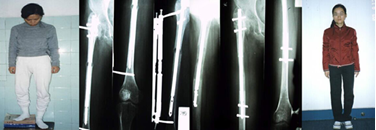

病例1:张某,女,14岁,化脓性骨髓炎后遗留缺损性骨不连,骨缺损约2.5 cm,肢体短缩约16.4 cm,膝关节强直,面临截肢。

病例2:患者,女,18岁,肢体短缩15cm,骨不连。

病例8:某女,18岁,化脓性骨髓炎致右股骨短缩13CM。